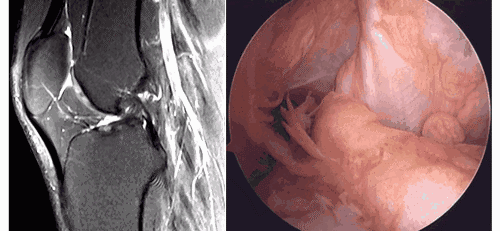

5.假瘤:韧带损伤后断端较整齐,残端组织增生并被滑膜包裹呈'瘤状',如果突出于前方为'独眼征',多见于韧带股骨附着部撕裂及部分撕裂。

12.jpg